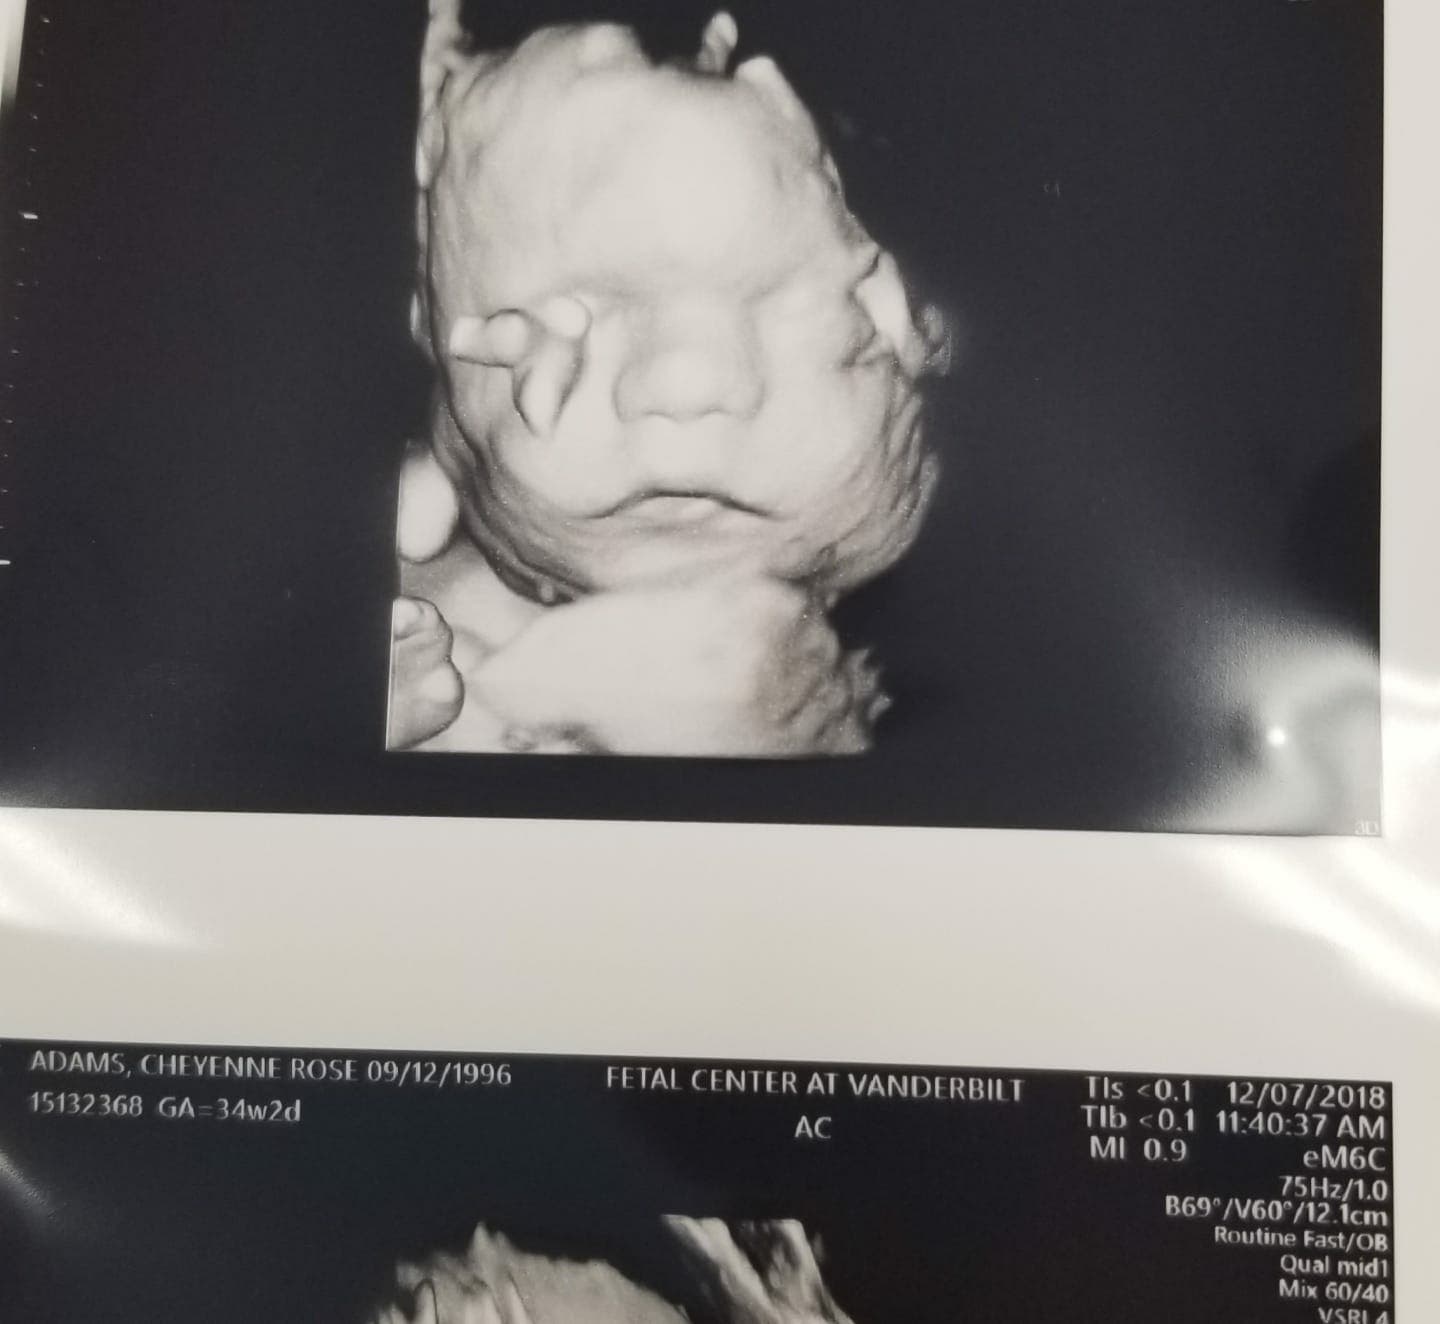

Chayenne Potts et son mari avaient hâte d’avoir leur premier enfant. Quand la femme est enfin tombée enceinte, elle éprouva un immense bonheur. Seulement, lors d’une consultationmédicale, le verdict a eu l’effet d’un véritablechoc.Les médecins ont informé le couple que le bébé souffrait d’une maladie des os connue sous le nom d’ostéogenèse imparfaite. Ainsi, ils ont déclaré qu’il était «brisé et cassé» et qu’il pouvait mourir pendant la grossesse, ou au plus une semaine après l’accouchement. Les médecins ont conseillé à Chayenne de se faire avorter.

Causée par une mutation des gènes du collagène de type I, l’ostéogenèse se caractérise par une fragilité et une faiblesse osseuse entraînantdes fractures à répétition. Cette maladie peut survenir à n’importe quel âge. Chez les adultes, elle peut être bénigne et exiger seulement la mise en place de certaines mesures pour éviter les risques. Cependant, les cas les plus sévères sont ceux qui surviennent lorsque le bébé est encore dans le ventre de sa mère. Ainsi, grâce à une échographie, les médecins peuvent repérer la maladie. Malheureusement, cette forme sévère peut entraînerunemortintra-utérine ou juste après la naissance. Si le bébé survit, il pourra êtresujetà plusieurs complications graves en étant enfant: déformation du thorax et des membres, ralentissement de croissance physique, fragilité dentaire et strabisme. En outre, à l’âge adulte, plus de50%des personnes souffrant de cette maladie subissent une perteauditive.